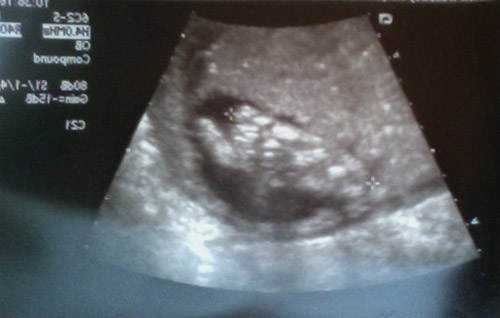

Front face shot — much less like Gollum.

Our last ultrasound was about a week and a half ago (I know, I know, I’m behind), and I’ve decided my baby looks like Gollum: